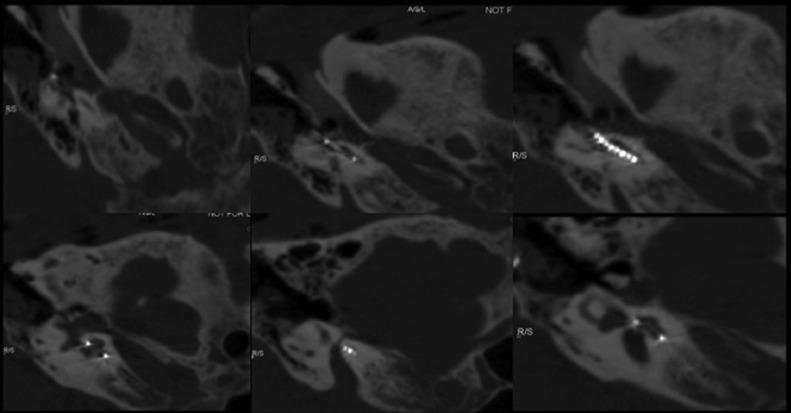

The cochlear implant is an implanted auditory prosthesis that can restore severe and profound hearing loss. About 20% of patients with congenital sensorineural hearing loss have a malformation of the inner ear. These abnormalities must be investigated before a cochlear implant because they can lead to intra and postoperative complications and/or anomalies. Most labyrinthine malformations are well known; some are less frequent and can be underdiagnosed at the preoperative computed tomography. This report presents the case of bilateral cochlear-facial dehiscence, bony dehiscence between the facial nerve labyrinthine segment, and cochlear basal turn. In our 56-year-old patient, this malformation was misdiagnosed before the cochlear implant and revealed afterward because of abnormal facial nerve stimulation during intraoperative electrophysiological checking.

人工耳蜗是一种可植入的听觉假体,能够恢复重度和极重度听力损失。约20%的先天性感音神经性听力损失患者存在内耳畸形。在植入人工耳蜗之前必须对这些异常情况进行检查,因为它们可能导致术中及术后并发症和/或异常。大多数内耳畸形是众所周知的;有些则较少见,在术前计算机断层扫描时可能漏诊。本报告介绍了一例双侧耳蜗-面神经裂缺的病例,即面神经迷路段与耳蜗底转之间的骨质裂缺。在我们这位56岁的患者中,这种畸形在人工耳蜗植入前被误诊,后来由于术中电生理检查时面神经刺激异常而被发现。